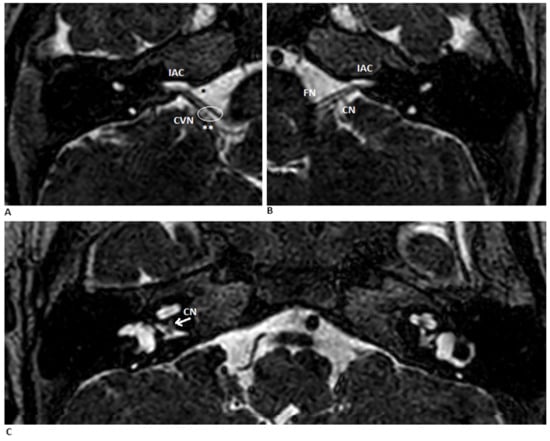

MRI demonstrated a normal facial nerve in the anterosuperior compartment and a common vestibulocochlear trunk dividing into three branches—one toward the cochlea and two toward the vestibule. The cochlear branch appeared markedly thin, consistent with cochlear nerve hypoplasia (Figure 2).

MR scan of the cerebellopontine angle. (A,B) Coronal T2-weighted MRIs of the right and left ears show a normal porus acousticus (**), the FN (*) and bilaterally narrow internal auditory canals (IAC). (C) Axial view shows bilateral hypoplastic vestibulocochlear nerves (CVN). The arrow the point where the cochlear portion of the CN branches off from the vestibular portion. Abbreviations: FN—facial nerve; CN—cochlear nerve.

The cochlear nerve measured 0.6 mm on the right side and 1 mm on the left. Inner ear structures were otherwise normal. Despite adequate hearing-aid fitting, auditory and speech perception remained poor, preventing age-appropriate language development. Therefore, an electrically evoked auditory brainstem response (EABR) was performed to guide further auditory rehabilitation and assess candidacy for cochlear implantation.